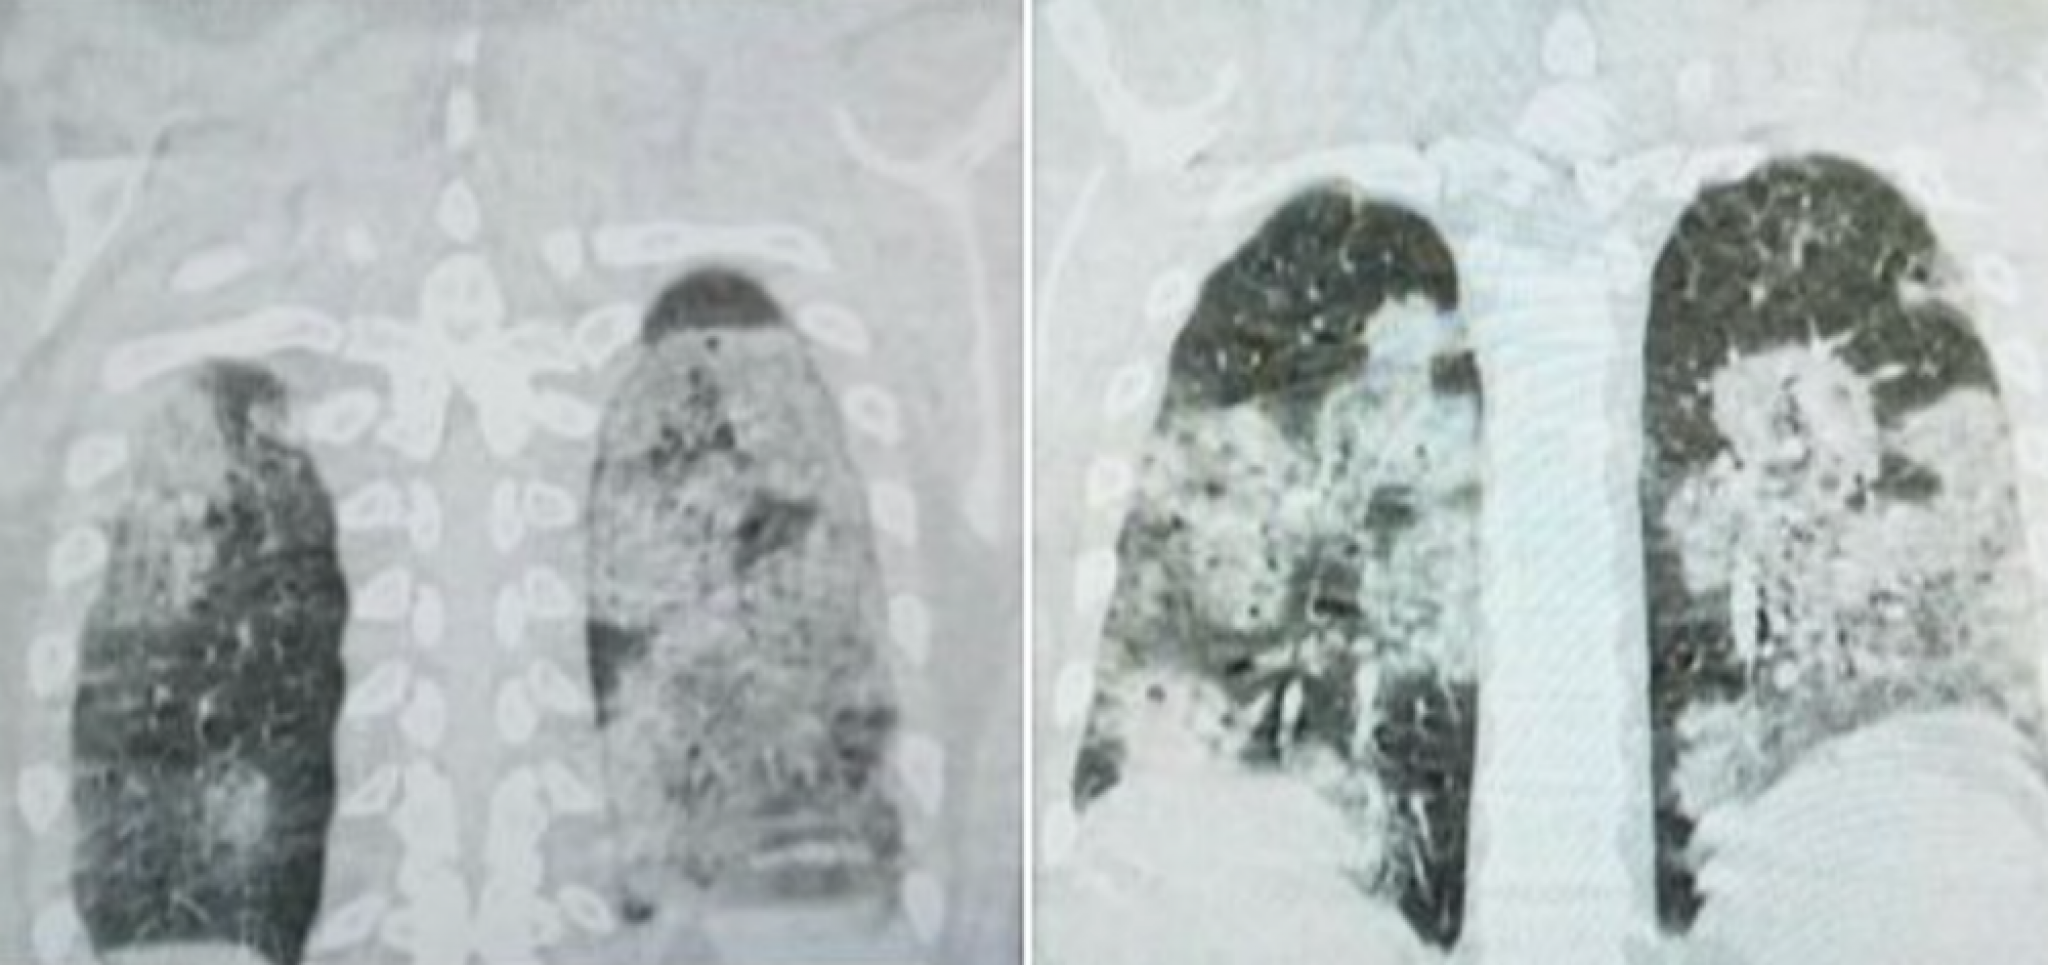

Sarajevski doktor Dragan Stevanović objavio je na Fejsbuku snimke pluća jednog od hospitalizovanih pacijenata koji je završio na kovid odeljenju.

On je objasnio da se radi o mladom, do tada zdravom čoveku koji je nepušač, a čija su pluća vidno stradala usled infekcije korona virusom.

– Za one koji ne znaju, zdrav je crni deo pluća – objavio je dr Stevanović.